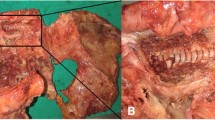

Fracture patterns in simulated trajectories TS1 and S1A were similar for all loading directions. Fracture initiation occurred at the screw tip in axial loading and in the trabecular bone, above (in extension) or below (in flexion) the screw (Fig. 6). Bi- and quad-cortical screws resulted in lower maximum bone stress compared to uni- and tri-cortical screws. For the sacroiliac trajectories, the fracture always occurred in two steps. Fracture initiation occurred in the ilium, subjecting the sacrum to higher force until final failure (Fig. 7).

Stress and fracture initiation of the trabecular bone for the S1AI with increasing flexion toggle force (F). Orange and red circles indicate high stresses and bone rupture, respectively. The fracture starts in the ilium, after which the sacrum withstands the load through the ligaments until fracture